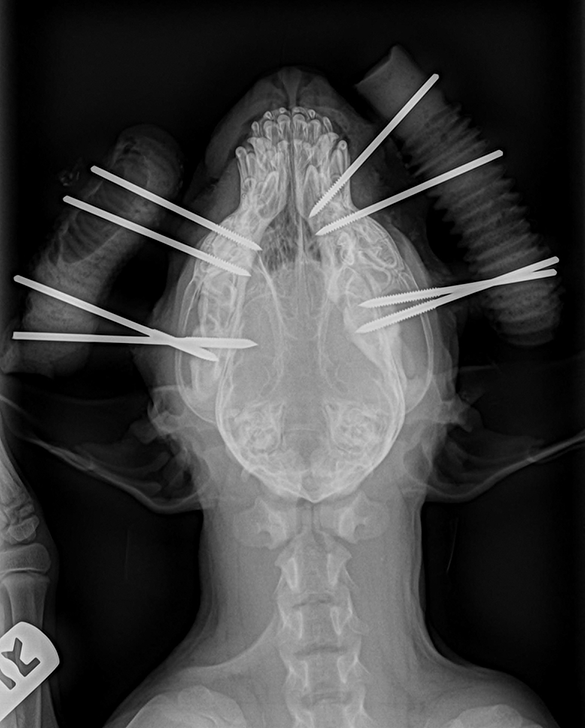

Dog Broken Jaw Surgery . Your dog’s veterinarian will give his or her. If your dog has an open or comminuted fracture, surgery is usually necessary to repair or replace the shattered. In these cases, surgeons frequently use metal plates, screws, and wires. Surgery is most often used to repair the fracture. Surgery is the most common treatment when it comes to repairing broken jaws in dogs. Occasionally, we have to use alternative methods to image or repair a complicated jaw fracture, but we will work together to find the right solution for your pet. Common traumatic events include vehicular trauma or an altercation with another dog. Oral surgery can be done to remove growths, repair oral defects, fix jaw fractures and in many cases remove teeth to relieve pain. What causes broken jaws in dogs? However, there are several methods to accomplish the surgical repair. Once an acrylic splint is in place, your pet will need to abstain from chewing on toys or anything hard for several weeks. At animal dental care and oral surgery, most mandibular fractures treated have occurred because of a trauma or as a result of periodontal disease.

Common traumatic events include vehicular trauma or an altercation with another dog. Oral surgery can be done to remove growths, repair oral defects, fix jaw fractures and in many cases remove teeth to relieve pain. However, there are several methods to accomplish the surgical repair. Surgery is the most common treatment when it comes to repairing broken jaws in dogs. Your dog’s veterinarian will give his or her. Surgery is most often used to repair the fracture. Occasionally, we have to use alternative methods to image or repair a complicated jaw fracture, but we will work together to find the right solution for your pet. Once an acrylic splint is in place, your pet will need to abstain from chewing on toys or anything hard for several weeks. At animal dental care and oral surgery, most mandibular fractures treated have occurred because of a trauma or as a result of periodontal disease. In these cases, surgeons frequently use metal plates, screws, and wires.